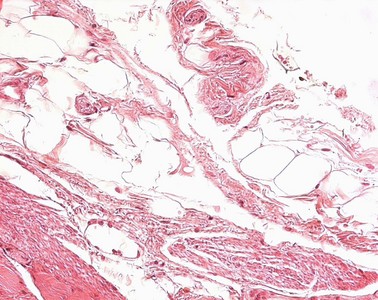

Präparat 3: Ösophagus (Mensch), Querschnitt, H.-E.

Tunica adventitia

besteht aus lockerem Bindegewebe und baut Organe, Arterien und Venen in die Umgebung ein. Im Verdauungstrakt findet sich eine Tunica adventitia in den Abschnitten, die nicht von einer Tunica serosa überzogen sind, also sekundär retroperitoneal oder extraperitoneal liegen.

äußerste Schicht der Organe des Gastrointestinaltraktes. Sie besteht aus lockerem Bindegewebe und verankert die nicht von einer Serosa bedeckten Organe in ihrer Umgebung. Neben Fettzellen finden sich versorgende Blutgefäße und Nerven.

Bindegewebe ist deutlich anders aufgebaut als Epithel. Im Epithelverband liegen die Zellen dicht an dicht, die Interzellularräume sind eng. Das Bindegewebe enthält weniger Zellen und große Interzellularräume. Die ortsständigen Zellen im Bindegewebe sind Fibroblasten/Fibrozyten. Außerdem kommen "freie" Zellen vor, die in das Bindegewebe einwandern oder es verlassen können und der Abwehr dienen. Die großen Interzellularräume des Bindegewebes enthalten Wasser und die extrazelluläre Matrix (amorphe Grundsubstanz und retikuläre, kollagene oder elastsiche Fasern), die von den ortsständigen Zellen gebildet wird. Bindegewebe ist im Körper weit verbreitet.

Univakuoläre Fettzellen

Adipozyten; bilden das weiße Fettgewebe. Jede Fettzelle enthält einen einzigen großen membranlosen Fetttropfen. Wird das Gewebe für histologische Routineuntersuchungen in Paraffin eingebettet, löst sich das Fett aus diesem Tropfen und es entsteht eine einzige, große Fettvakuole. Zellkern und Zytoplasma werden durch den Fetttropfen an den Zellrand gedrängt, es entsteht das Bild der Siegelringform der Fettzelle.

Die Tunica adventitia verankert die Speiseröhre in ihrer Umgebung. Sie besteht aus lockerem Bindegewebe, in ihr sind univakuoläre Fettzellen eingelagert.